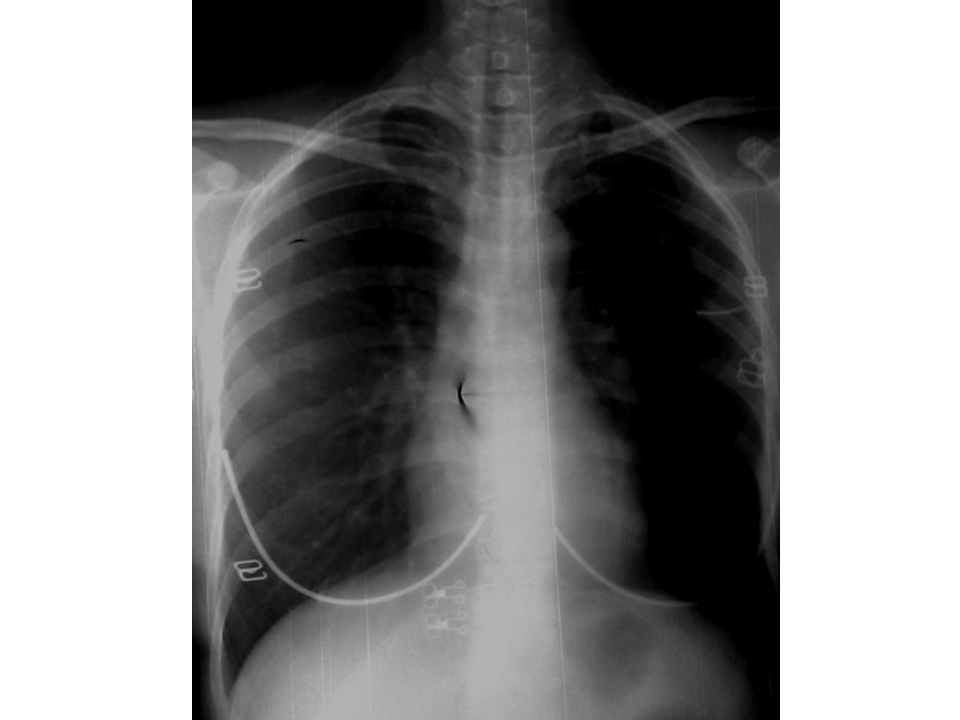

VIETNAMESE MEDIC ULTRASOUND CASE 193 MEDIC RADIOLOGY CASE 07 Tracheobronchomalacia Ct Acquired tracheomalacia is a common finding, seen in approximately 10% of ct and up to 23% of autopsy and bronchoscopy series 5. Learn about tracheobronchomalacia (tbm), a condition where your airways collapse and close down, causing breathing problems. There is increasing recognition of tracheobronchomalacia (tbm) in patients with respiratory complaints, though its true. A dynamic ct scan of the trachea. Tracheobronchomalacia Ct.

VIETNAMESE MEDIC ULTRASOUND CASE 193 MEDIC RADIOLOGY CASE 07 Tracheobronchomalacia Ct Learn about tracheobronchomalacia (tbm), a condition where your airways collapse and close down, causing breathing problems. Tracheobronchomalacia (tbm) refers to airway collapse due to typically excessive posterior membrane intrusion and. A dynamic ct scan of the trachea and carina confirmed expiratory airway collapse that was more marked on the left (see fig. Acquired tracheomalacia is a common finding, seen in. Tracheobronchomalacia Ct.